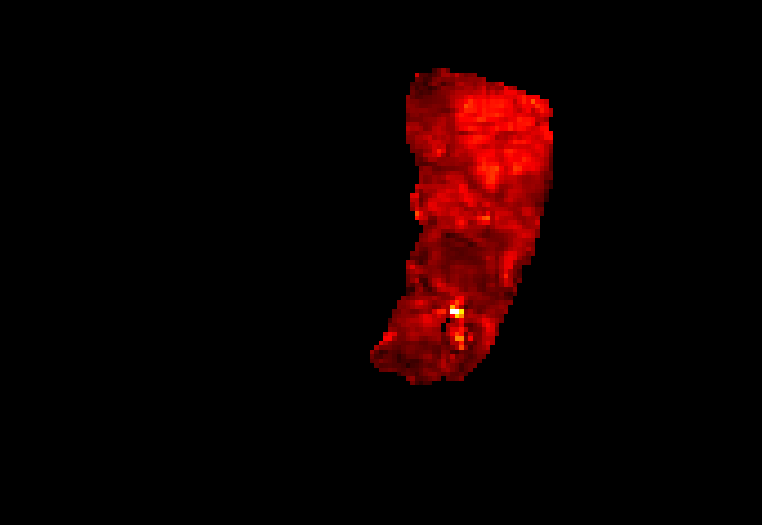

Display description: All placentae are shown in maternal coronal plane (See A). The slice with the largest placental volume was chosen. The same colormap was chosen for all placentae (See B).